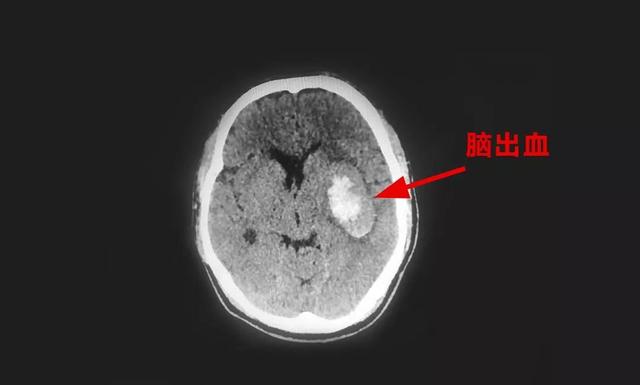

后脑勺痛可能是枕大神经痛,紧张性头痛,或者是因为脑部肿瘤,脑出血等

中年企业主三夜不寐突发脑出血 术后直言"不敢再这么拼了"